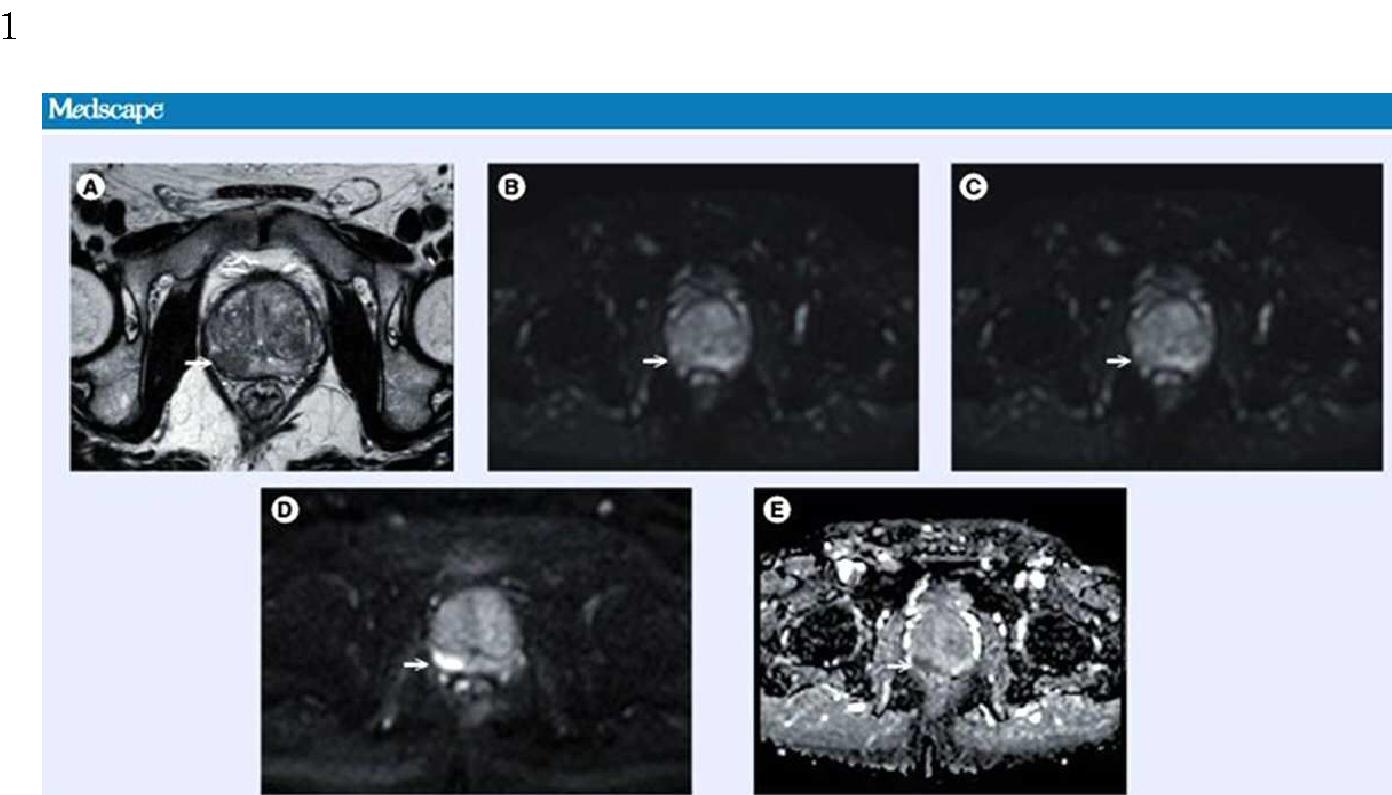

전립선암 진단에 관한 정보제공방법